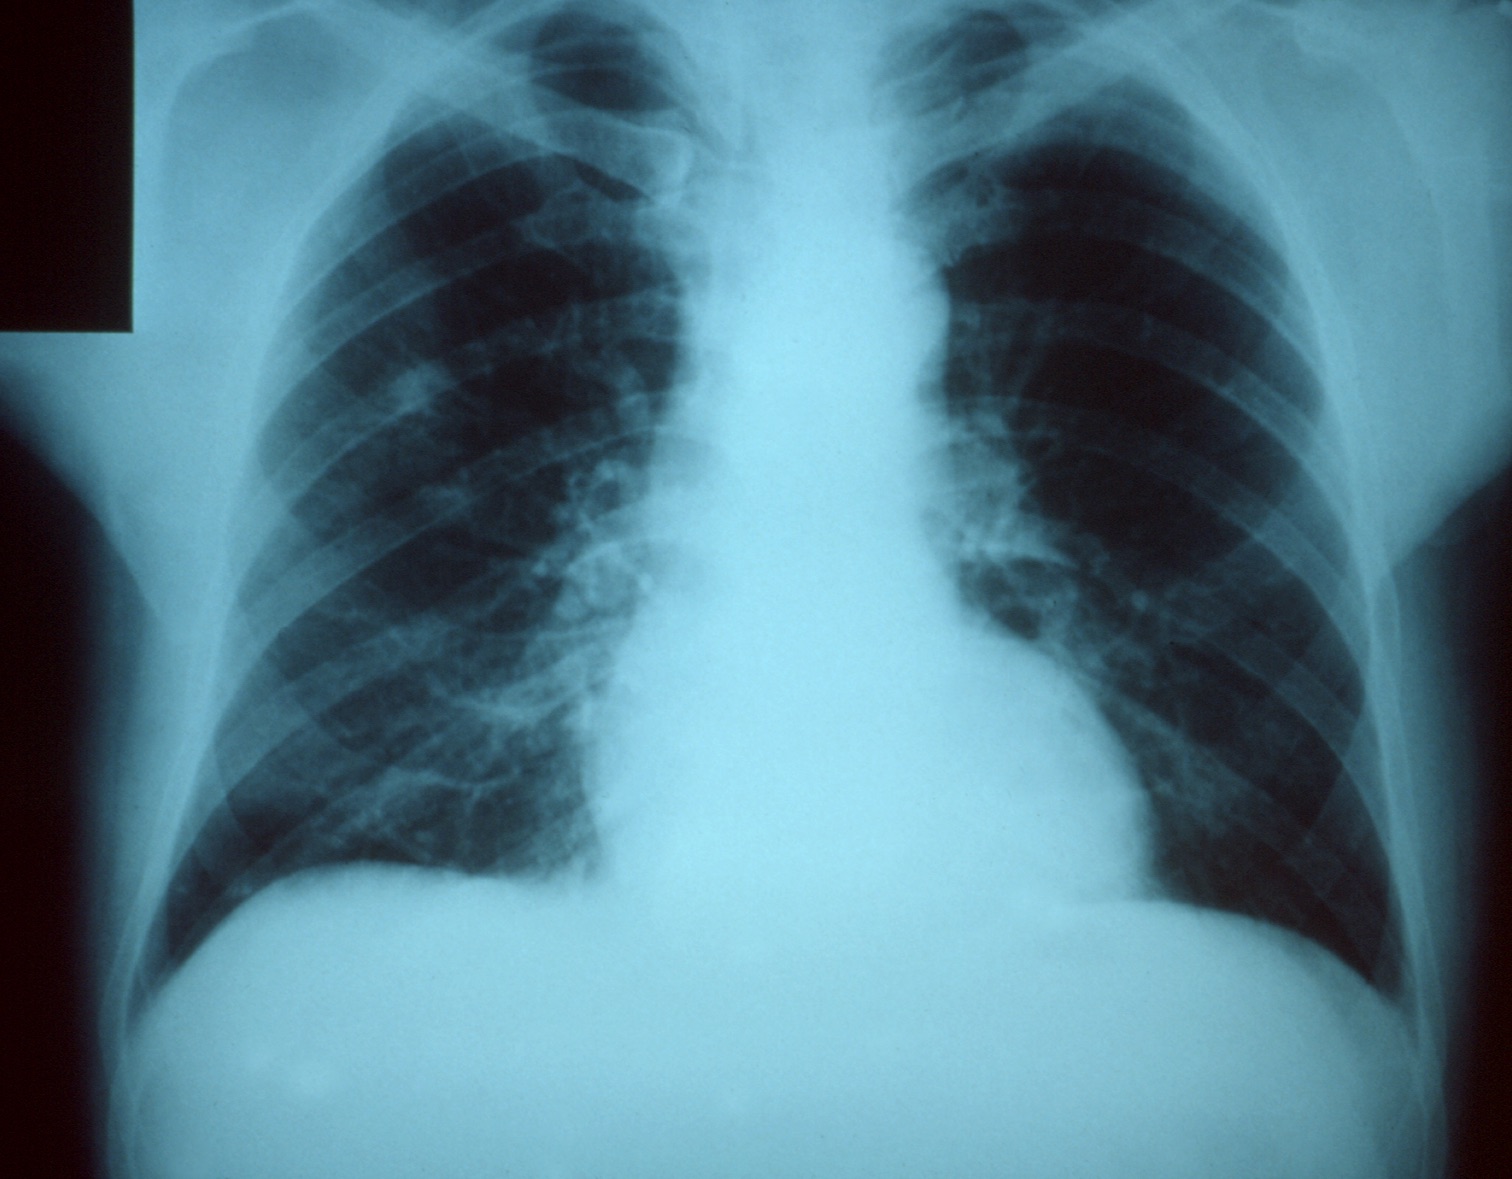

In the lungs, for example, swelling can prevent oxygen from reaching your blood vessels. Oxygen normally moves across very thin membranes in endless moist chambers inside the lobes of your lungs. When that tissue becomes swollen with immune cells, it’s much harder for oxygen to reach the tiny blood vessels that it’s supposed to move into. There’s also some degree of damage to the lung tissue. Viruses can’t replicate by themselves, so they have to do it inside your cells instead. That means that in order to kill the virus, your immune system has to destroy your body to some extent, which only makes oxygenation harder.

About a third of people who die from the flu do so directly. That is, they die from the effects of the virus (and the effects of their bodies trying to fight it off). Respiratory failure—when your lungs simply can’t get enough oxygen—is one of the most common ways. It’s also one of the fastest. Direct deaths from the flu occur quickly, often within a few days, and with little warning.

But when your immune system is already flagging under the weight of a viral infection, those bacteria can spread to the lungs and take hold. This is called a secondary infection, and when it occurs in the lungs we call it pneumonia. Unlike a direct death, secondary pneumonia acts more slowly. Often you’ll start to feel better after a few days with the flu virus as your body starts to fight it more effectively. And then, suddenly, you’ll feel a lot worse. The bacteria have bided their time and are now multiplying rapidly inside your lungs, and your already exhausted immune system is struggling to keep up.